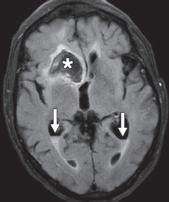

图 1A —大脑中动脉 (MCA) 梗塞。早期 MCA 梗死的平扫 CT 图像显示右侧豆状核轻微水肿,豆状核由壳核(白色箭头)和苍白球(黑色箭头)组成。

图 1B —大脑中动脉 (MCA) 梗塞。亚急性 MCA 梗塞的平扫 CT 图像显示细胞毒性水肿,导致左侧岛叶带缺失(箭头)。

图 1C —大脑中动脉 (MCA) 梗塞。平扫 CT 图像显示右侧 MCA 高密度征(箭头)。

急性动脉梗塞会产生缺氧状态,伴随去极化、炎症、氧化或亚硝化应激以及细胞凋亡继发的 ATP 快速消耗。细胞毒性水肿在动脉闭塞后 30 分钟内出现,在梗塞后 24 至 72 小时达到峰值,并在再灌注后持续长达 24 小时。在 CT 上,灰白质界限的丧失发生在对应的血管分布位置。大脑中动脉梗死的早期迹象包括豆状核的遮蔽(图 1A )) 和岛带的丢失 (图 1B); 这些通常具有高灰白对比度的区域由小的脑动脉穿支供血。大的血管内血栓也可能表现为类似增强扫描的密度增高(高密度动脉征)(图 1C )。进行性水肿导致病灶整体体积增加,表现为脑沟、脑室和脑池的消失。